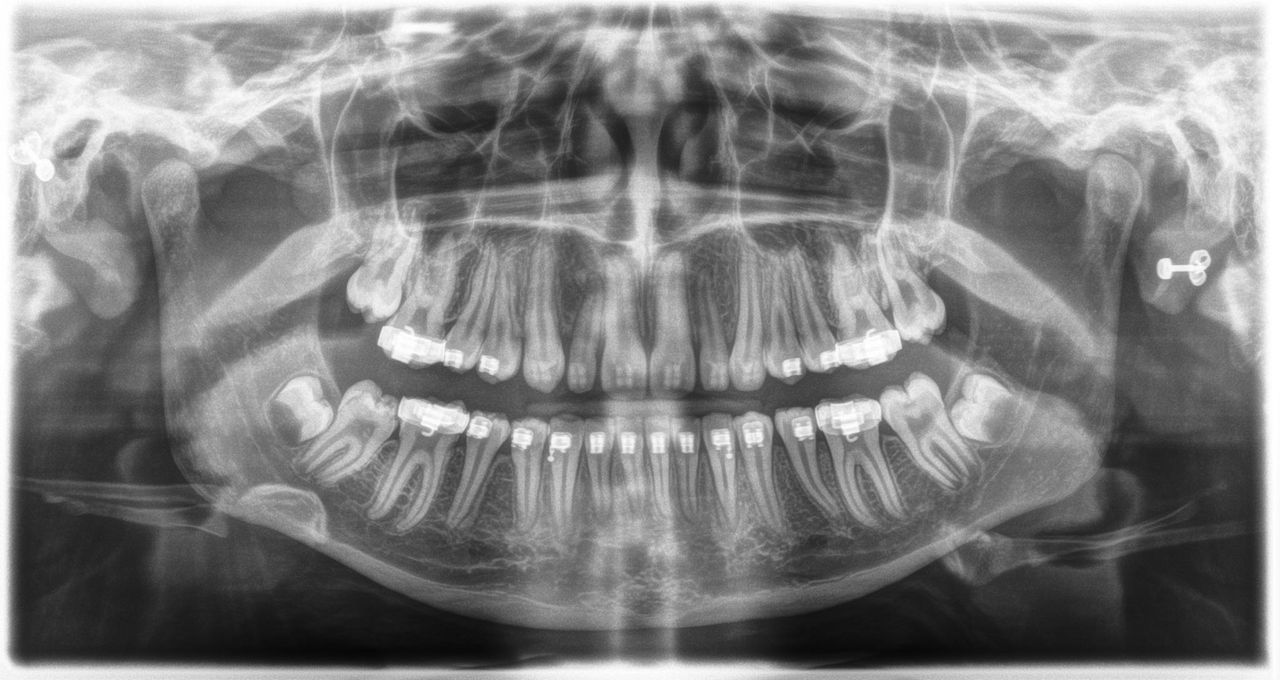

L’unité de radiographie 2D permet de s’immerger facilement dans le monde de l’imagerie numérique. Grâce à la technologie de capteur CsI et à son interface simple, vous bénéficiez de diagnostics fiables à chaque fois. L’option céphalométrique fait également de l’Orthophos E un partenaire fiable pour l’orthodontie. Dotez votre cabinet d’une large gamme de services qui ne sont possibles qu'avec l'imagerie numérique.

Pour les diagnostics de base en 2D